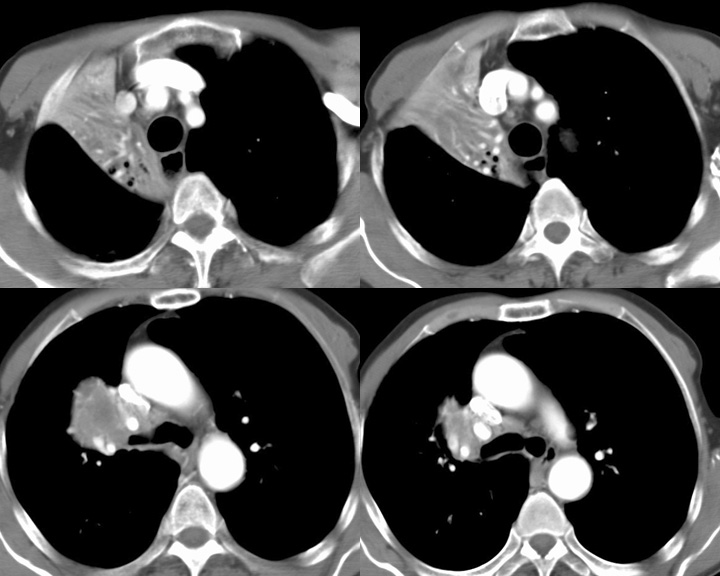

RUL Collapse Case 3 CT 4in1

Date: 02/28/2004